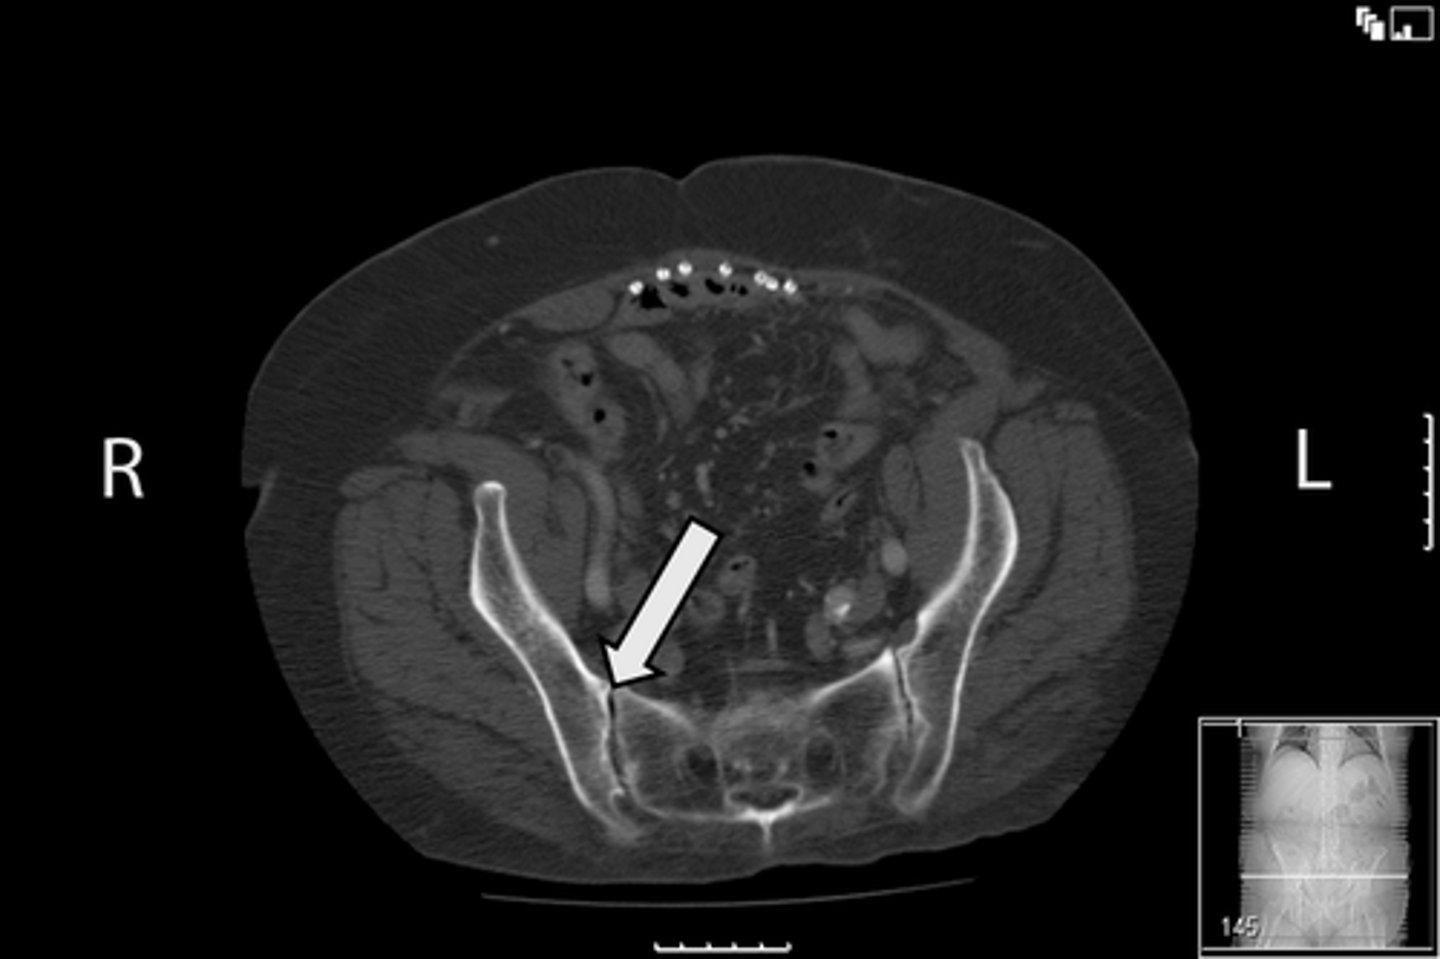

77

New cards

Axial male pelvis CT

What is the image?

<p>What is the image?</p>

78

Descending colon/sigmoid colon juncture

What is indicated in the image?

<p>What is indicated in the image?</p>

79

L external iliac artery

80

L gluteus muscle

81

L iliopsoas muscle

82

L internal iliac artery

83

Posterior aspect of L iliac bone

84

L sacroiliac joint

85

R common iliac artery

86

R gluteus muscle

87

R iliacus muscle

88

Posterior aspect of right iliac bone

89

R psoas muscle

90

R sacroiliac joint

91

R and L rectus abdominis